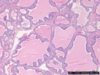

Identify ?

Graves disease-

Autoimmune condition.

- is the most common cause of hyperthyroidism

- incidence peaks between 30 and 50 years of age, more in females

- activating autoantibodies of the IgG1 subclass that are directed against the thyrotropin receptor are both specific for and central to Graves’ disease

- these antibodies stimulate thyroid hormone production that is uncontrolled by the hypothalamic–pituitary axis. Activating antibodies mimic the actions of thyrotropin at its receptor through the initiation of similar, but not identical, signaling

Microscopy-

Papillary projection & columnar epithelial lining with scaloping edges.